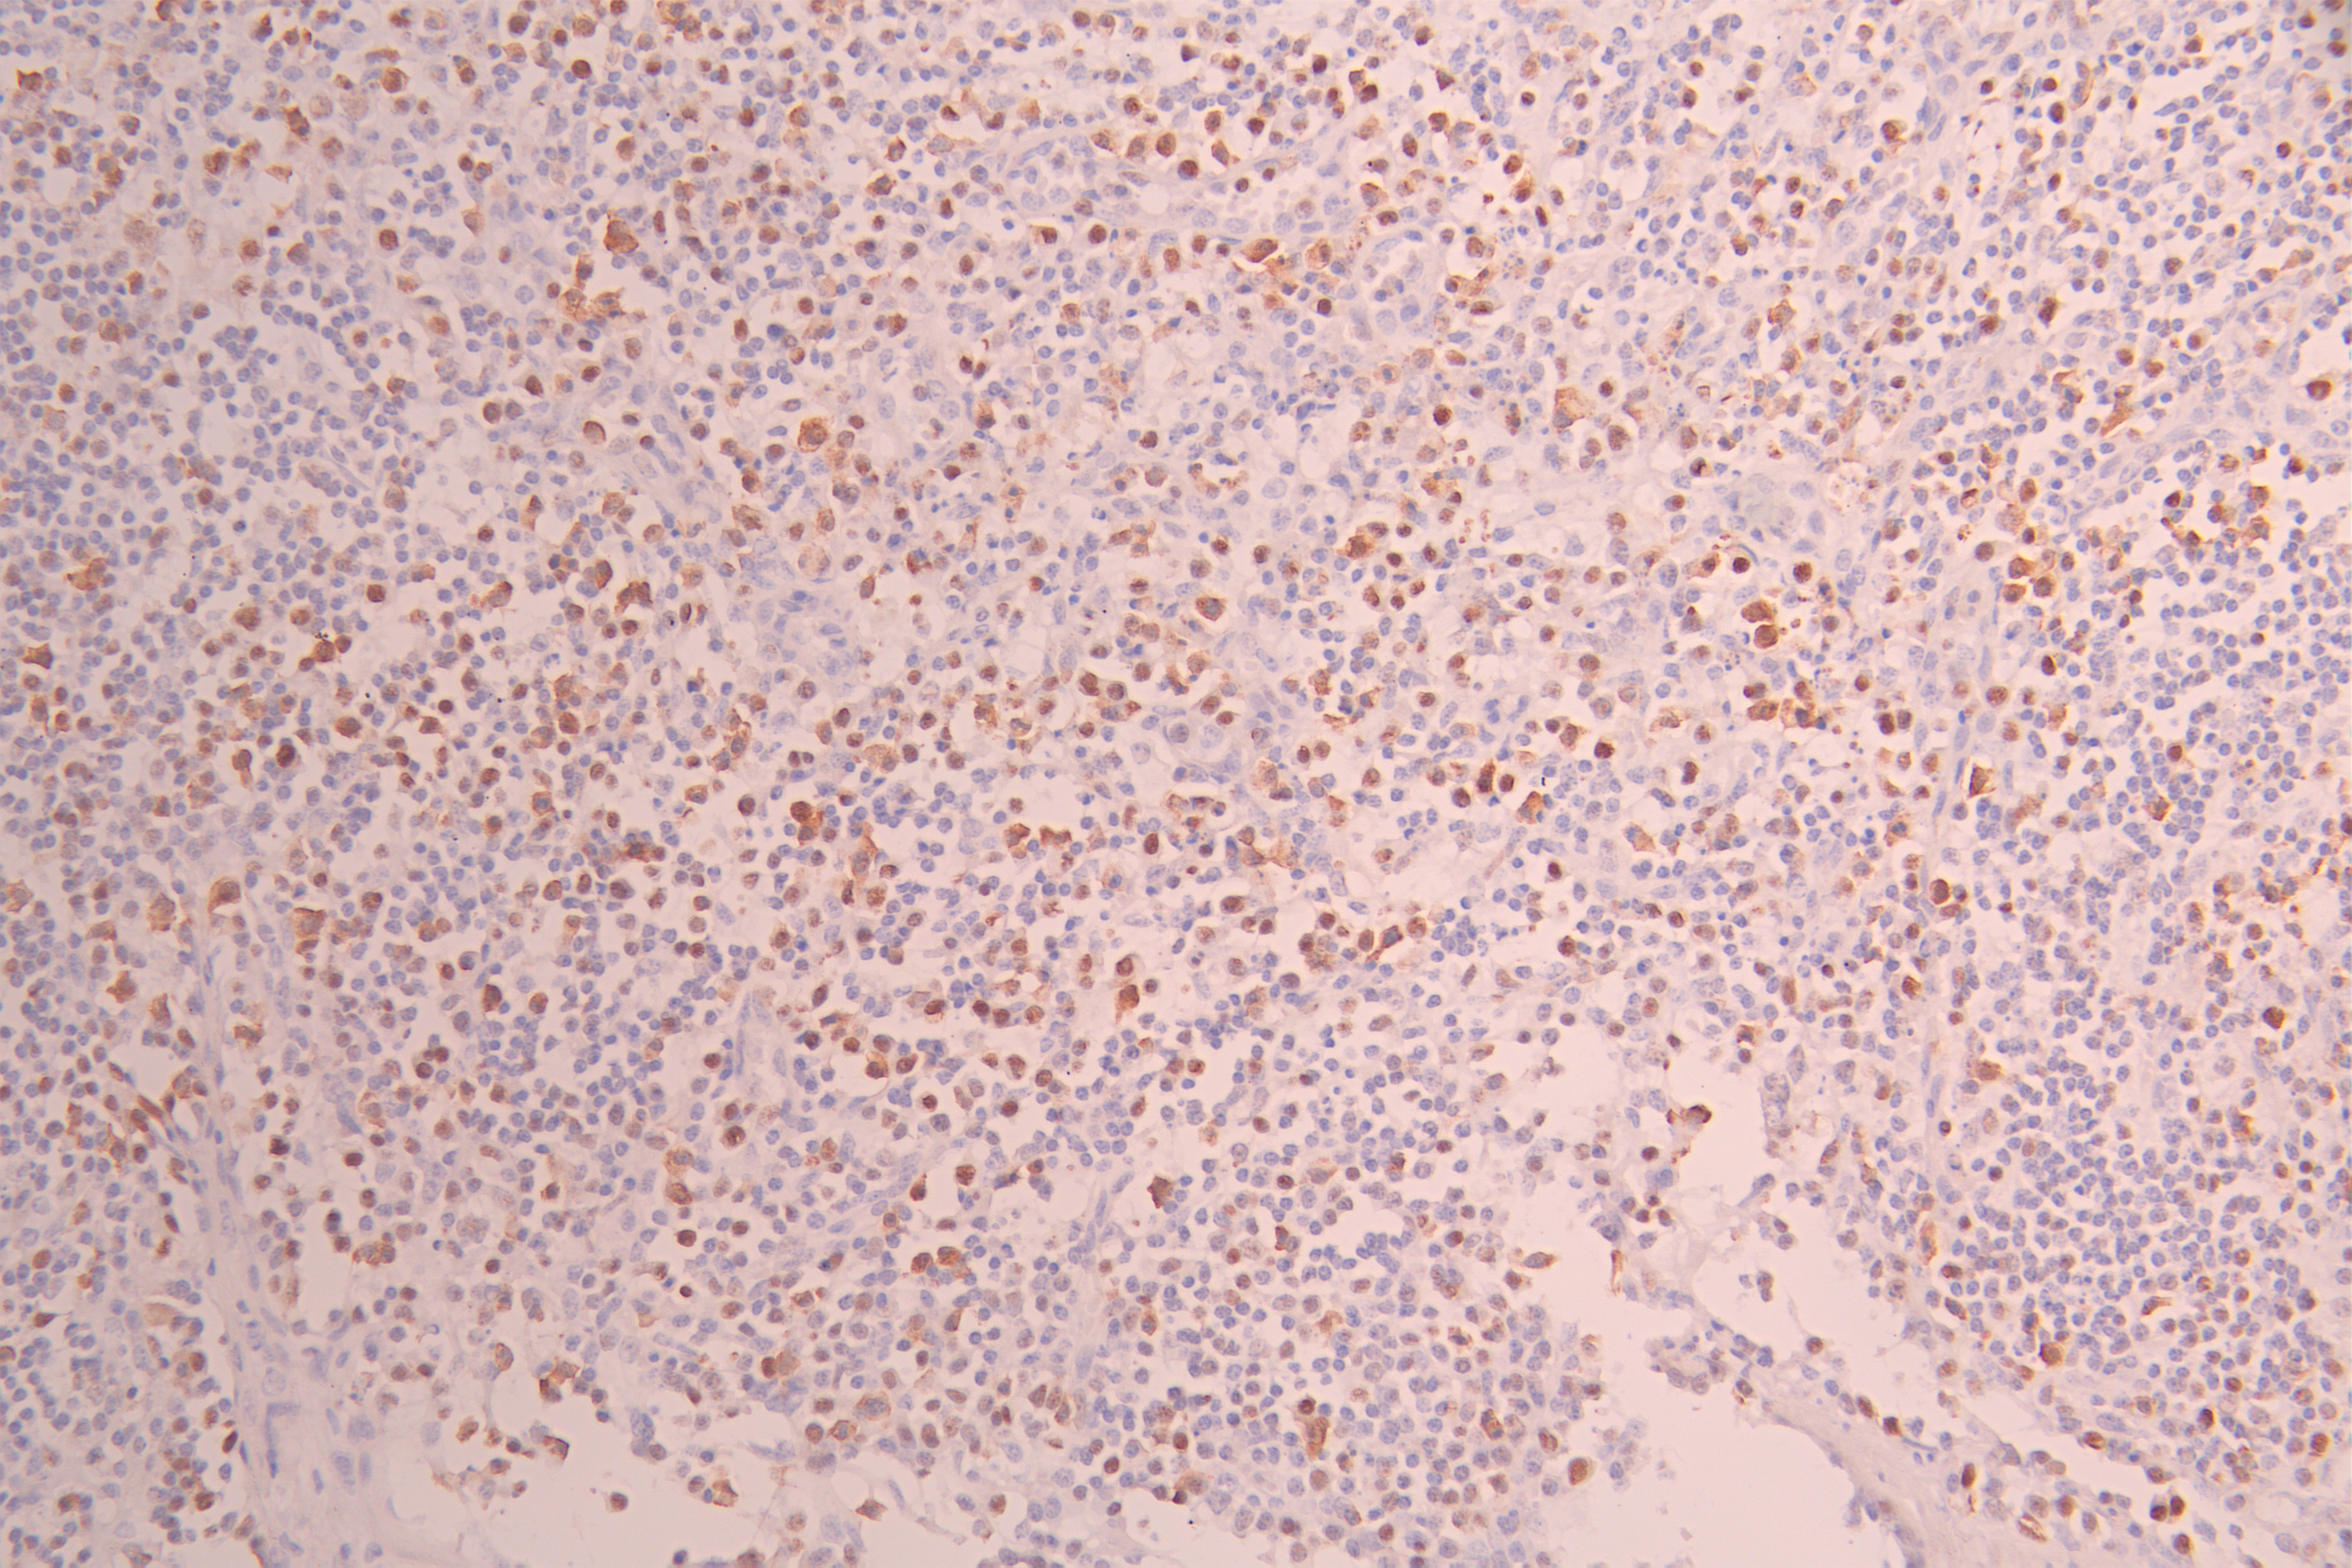

IHC image of CSB-RA237021A0HU diluted at 1:100 and staining in paraffin-embedded human lymph node tissue performed on a Leica BondTM system. After dewaxing and hydration, antigen retrieval was mediated by high pressure in a citrate buffer (pH 6.0). Section was blocked with 10% normal goat serum 30min at RT. Then primary antibody (1% BSA) was incubated at 4°C overnight. The primary is detected by a Goat anti-rabbit polymer IgG labeled by HRP and visualized using 0.05% DAB.